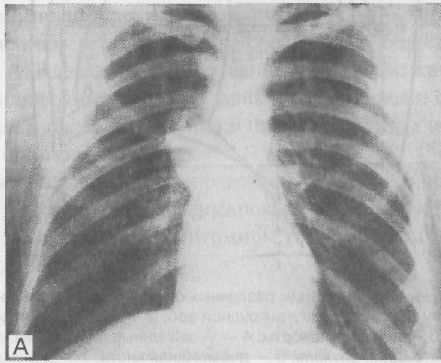

Типичная локализация липом — правый кардиодиафрагмальный угол. Растут липомы

медленно и только при очень больших размерах или при двустороннем распространении

приводят к сдавления жизненно важных органов и сосудов грудной полости. Малигнизация

отмечается крайне редко. Рентгенологически липома кардиодиафрагмального угла

выявляется как полукруглая тень, примыкающая к тени сердца, диафрагме и передней

грудной стенке.

Липомы в большинстве наблюдаются у женщин, склонных к полноте. Типичная локализация липом — правый кардиодиафрагмальный угол, хотя онн могут располагаться и в других отделах средостения. Рентгенологическая картина при липомах карднодиафрагмального угла характеризуется полукруглой тенью, примыкающей к тени сердца, диафрагме и передней грудной стенке. Дифференциальная диагностика между липомой средостения, целомической кистой перикарда и диафрагмальной грыжей Ларрея проводится в основном наложением пневмомедиастинума: газ окружает липому и расслаивает ее на дольки. Этот "симптом дольчатости" и отсутствие ножки, уходящей под диафрагму, патогномоничны для липом средостения.